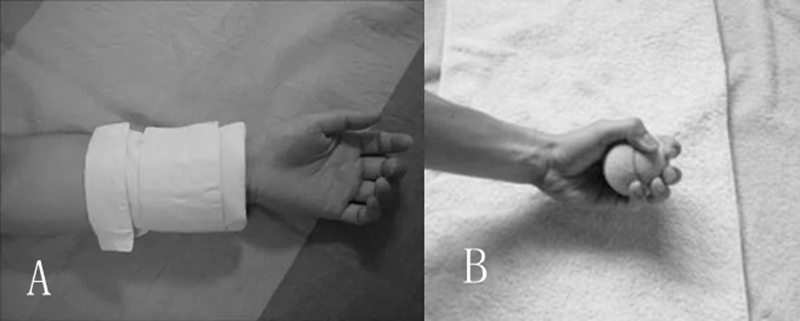

受伤第二周至第四周:①固定、冰敷;②热敷;③等长肌力训练;④主动关节活动

A.热敷;B.等长肌力训练

主动的关节活动

受伤第四周至第六周:①固定、冰敷、热敷;②肌力训练;③伸展

受伤第六周:①冰敷、热敷、肌力训练、伸展;②本体感觉训练